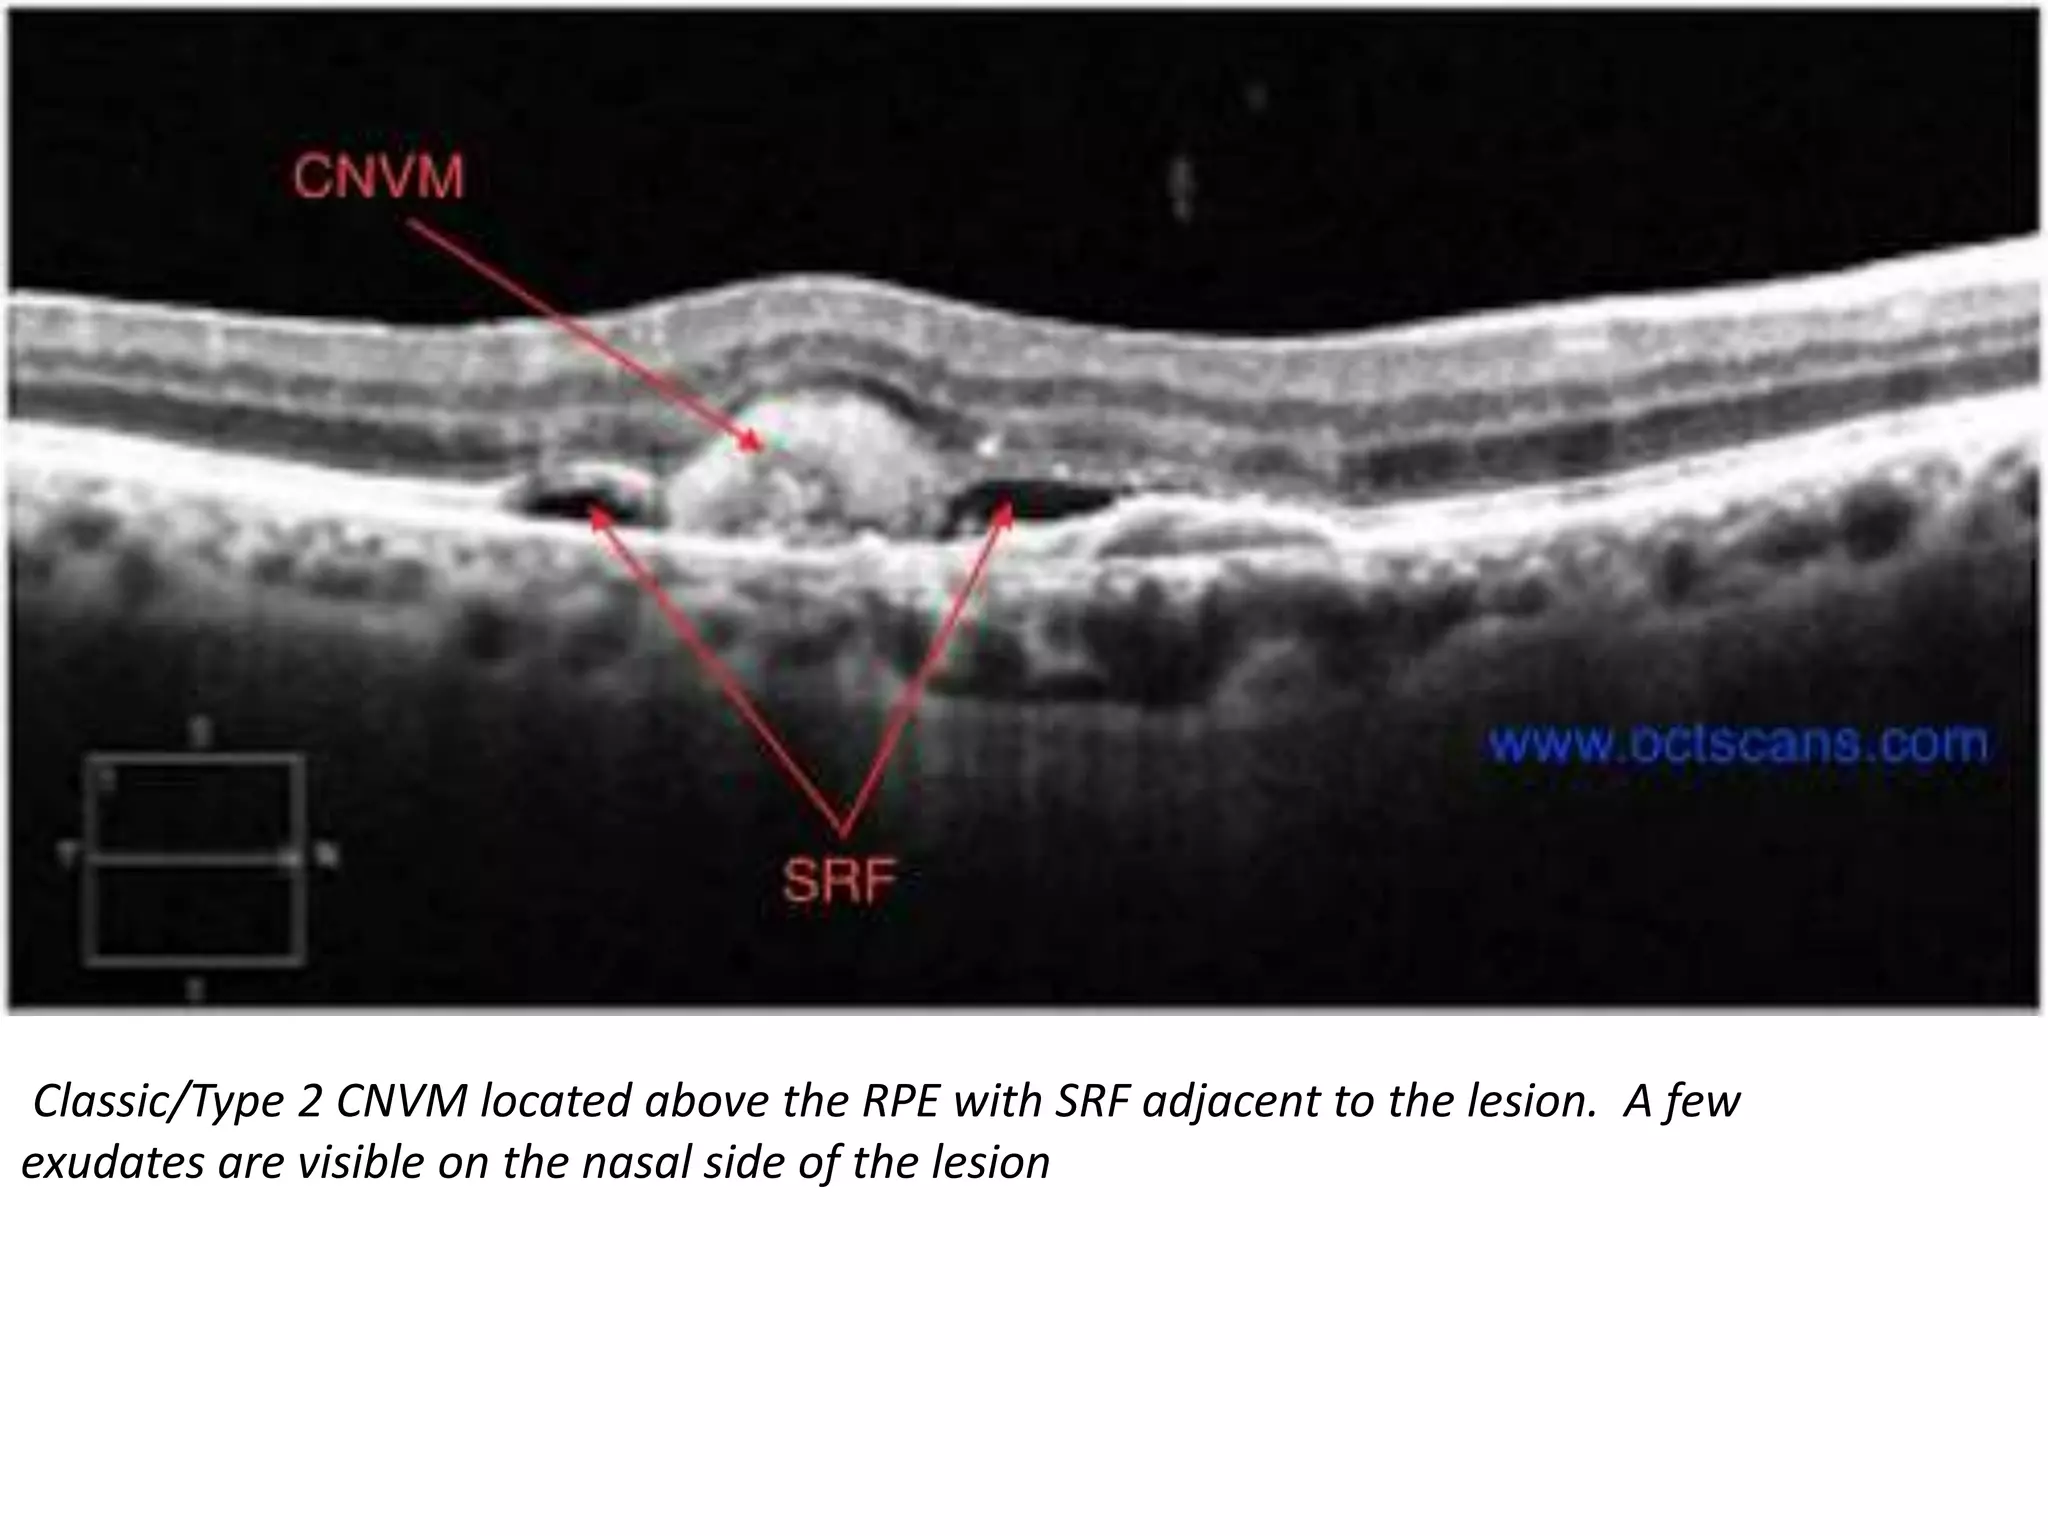

Classic/Type 2 CNVM located above the RPE with SRF adjacent to the lesion. A few

exudates are visible on the nasal side of the lesion

Classic/Type 2 CNVMlocated above the RPE with SRF adjacent to the lesion. A few exudates are visible on the nasal side of the lesion